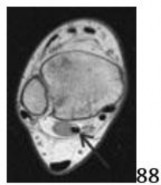

52a 52b 52c Figures 52a through 52c show the axial, coronal, and sagittal T2-weighted MRI scans respectively of a knee. The highlighted structure represents what anatomic finding?

5. # Transverse meniscal ligament

DISCUSSION: The images show a transverse meniscal ligament, which connects the anterior horns of the medial and lateral menisci. On sagittal images, the interface of this structure with the anterior horn of the lateral meniscus often simulates a tear. Following this structure over several successive images is helpful in identifying it as a normal structure. There is no abnormal signal within the menisci to suggest a tear. A meniscofemoral ligament is a posterior structure. A ligamentum mucosum or infrapatellar plica is best seen on the sagittal image and runs from the intercondylar notch to the anterior fat pad. The Preferred Response to Question # 52 is 5.